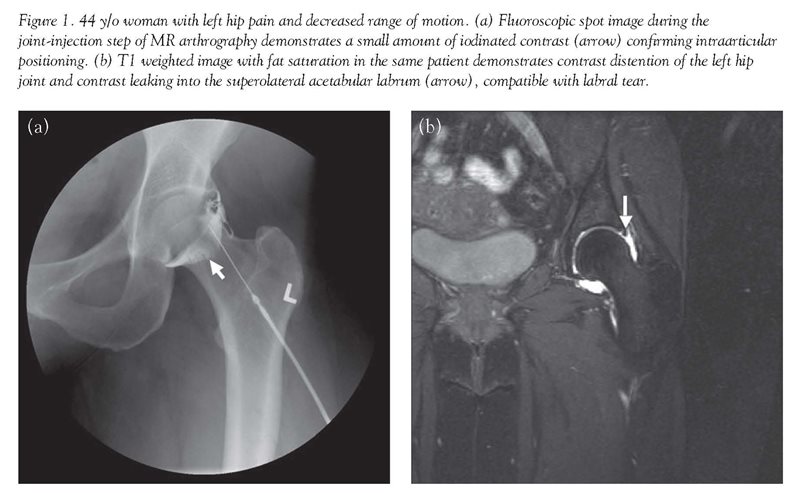

Unlike routine MR imaging, direct MR arthrography is a two step procedure that first requires joint injection. This minimally invasive procedure is typically well-tolerated and usually is performed with fluoroscopic guidance. After sterile preparation and local anesthesia, a 22g-25g needle is inserted into the joint. The use of fluoroscopy allows confirmation of the intra-articular position of the needle [Fig. 1]. This prevents injection of contrast solution outside the joint which could limit evaluation or mimic pathology. Following contrast injection, MR imaging is performed using a combination of T1 and T2 weighted sequences with and without fat suppression. (T1 and T2 are technical terms that refer to two different properties of spinning hydrogen atoms in a magnetic field. Suffice it to say that these are measured by MR and used to reconstruct an image of the tissue.)

As in the shoulder, a primary role of MR arthrography is in the evaluation of the labrum and labro-ligamentous complex—the fibro-cartilaginous structure which helps provide stability of the joint.[5] Labral tear can be a cause of persistent hip pain and disabling mechanical symptoms, and may ultimately lead to early osteoarthritis. Whereas conventional radiography, physical exam, and MR imaging can assess for pathology such as fracture, avascular necrosis, arthritis, and synovitis, they have not proven useful in evaluating labral tears. As in the shoulder, intra-articular contrast material can distend the joint capsule and extend into labral defects, outlining small labral tears [Fig. 1].[6]